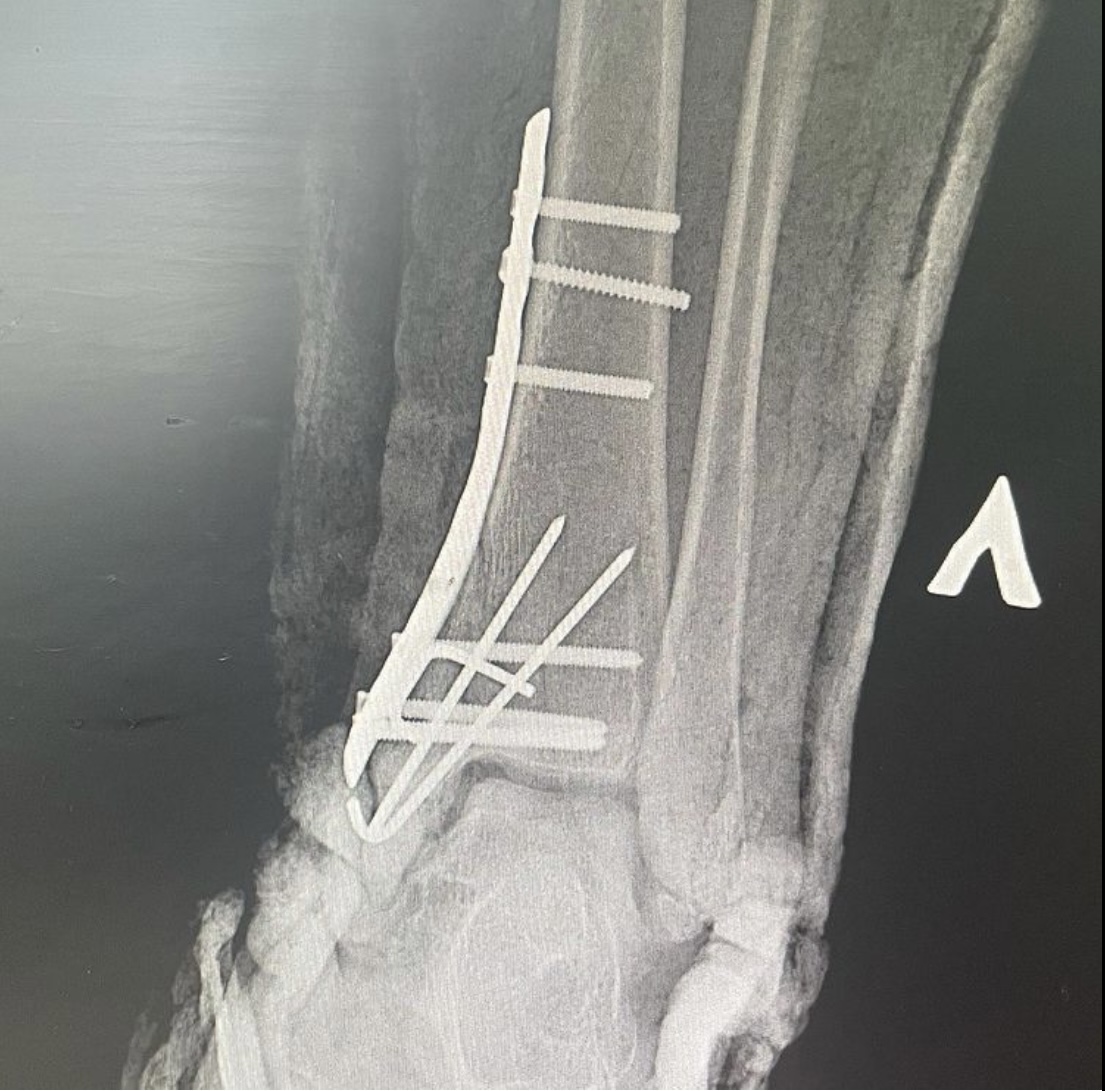

Врач – травматолог – ортопед 7-ой Городской клинической больницы Руслан Ильгизарович Закиров показывает рентген-снимки переломов, которые получили пациенты во время езды на самокате.

Во втором случае девушка 23 лет получила оскольчатый перелом дистального эпиметафиза большеберцовой кости. Также выполнен остеосинтез пластиновинтами и спицами. Данный случай осложнялся наличием внутрисуставного перелома с импрессией суставной поверхности.